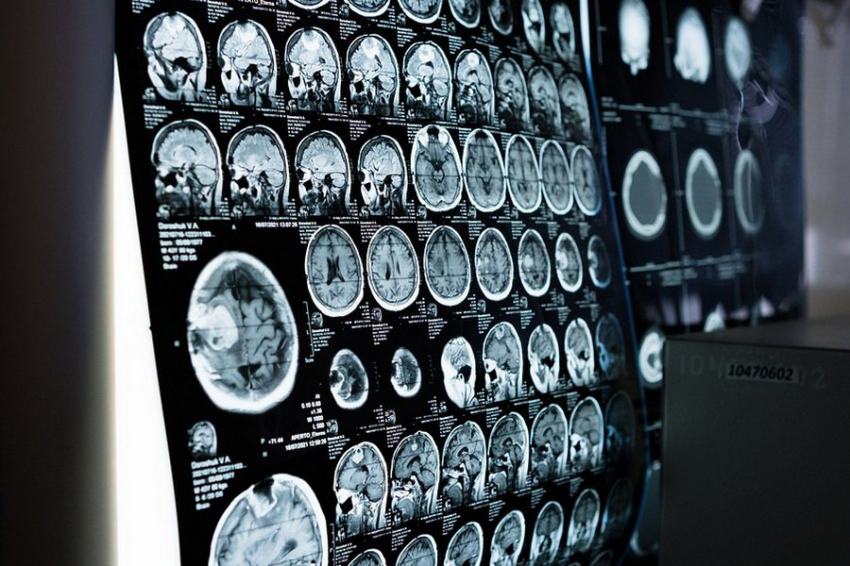

Командой был проведен анализ данных 27 400 человек, их средний возраст составлял 55 лет. Всем испытуемым провели сканирование мозга, а они рассказали исследователям, сколько времени в среднем проводят на солнце ежедневно.

С применением машинного анализа ученые произвели сравнение различий в структурных маркерах мозга с учетом ряда иных факторов окружающей среды, здоровья и социализации.

В результате была выявлена тревожная тенденция: у испытуемых, сообщивших о более длительном пребывании под солнцем, оказался меньший объем мозга и повышенная интенсивность белого вещества. А эти маркеры считаются характерными для старения мозга и связаны со снижением когнитивных способностей.

У тех, кто находился под воздействием солнца более трех часов в сутки, наблюдалось заметное уменьшение общего объема мозга, а также белого и серого вещества в сравнении с теми, кто был на солнце меньше времени. Эффект был сильнее всего выражен у мужчин, а также у участников эксперимента моложе 60 лет.